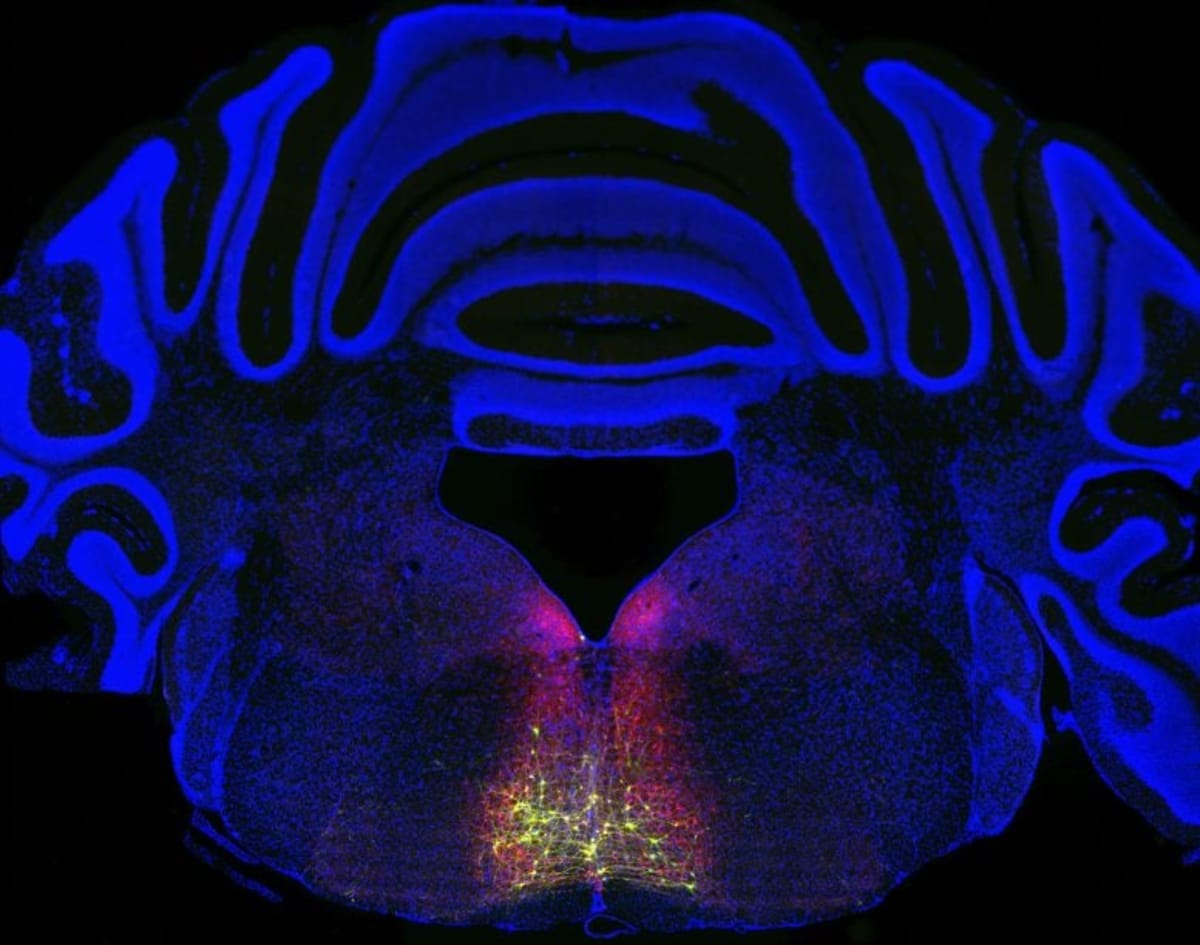

The research started with neurons in a brain region called the rostral ventromedial medulla. Using fluorescent markers, scientists traced a loop that starts in the spinal cord, passes through the thalamus and cortex, then circles back to the spinal cord. This circuit only activates after injury or inflammation, never during normal pain experiences.